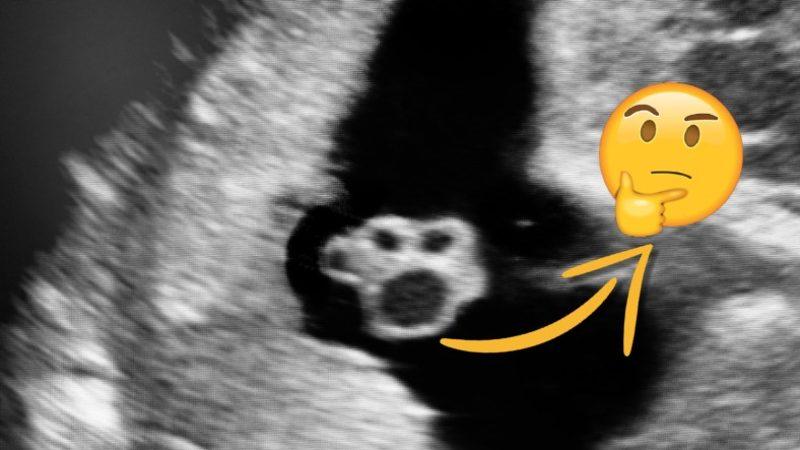

Evet! Patiye benzeyen bu görüntü aslında bir "göbek kordonu".

Muşta yutmuş birinin midesi gibi de anlaşılabilen bu ultrason görüntüsü, aslında anne babalarımızın üniversite bahçelerine bir heves gömdüğü göbek bağı.

Ayrıca bir venin oksijenli kanı taşıması ve arterlerin (atardamarların) oksijensiz kanı taşıması biyolojimizde alışıldık bir durum değildir. Göbek bağında diğer organlardan farklı olarak 2 arter ve 1 ven bulunması ortaya sevimli patiye benzer bir görüntü çıkarıyor.